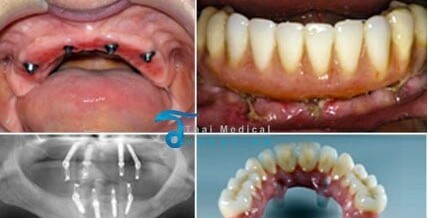

DENTAL CARE & AESTHETIC MIDDLE adalah klinik gigi dengan dokter - dokter gigi spesialis, yang